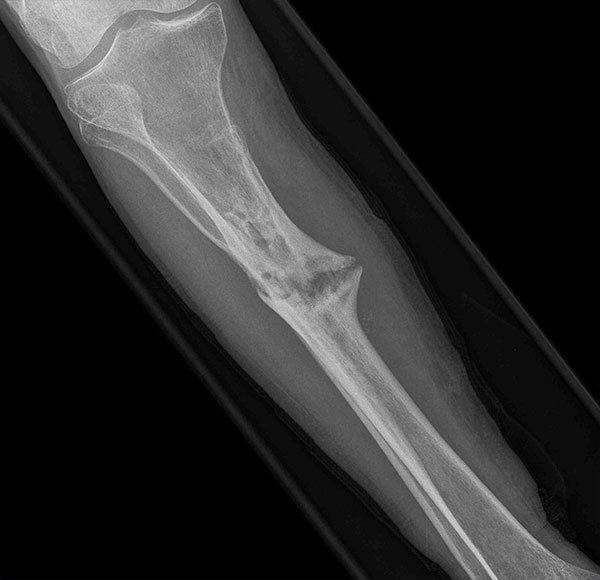

- Focus Area Reconstructive Surgery & Non-Surgical Management to Improve Bone Healing

- Sponsor DoD PRORP

- Primary Objective To define a serum protein based diagnostic for the progression and failure of fracture healing, though the identification of a set of serum proteins that appear at early times of biological healing and show a specific correlation with later radiological and functional signs used to define delayed healing and non-union.